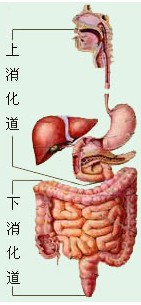

| 2021年7月26日 (一) 20:03 | 消化道.jpg (文件) |  |

16 KB | Uploaded with SimpleBatchUpload | 3 |